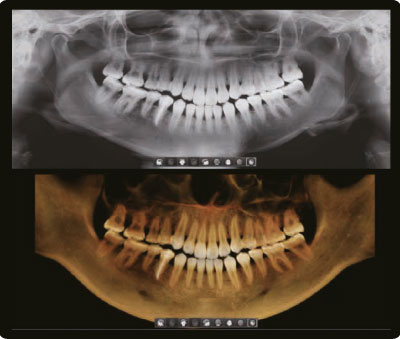

2D и 3D за одно сканирование, в одном приложении

Томограф Smart Plus предоставляет возможность проведения компьютерной томографии и получения панорамного снимка одновременно. Это позволяет сократить дозу облучения для пациентов. Кроме того, все полученные изображения доступны для просмотра в едином приложении, что упрощает диагностику, объяснение клинической ситуации и планирование лечения.